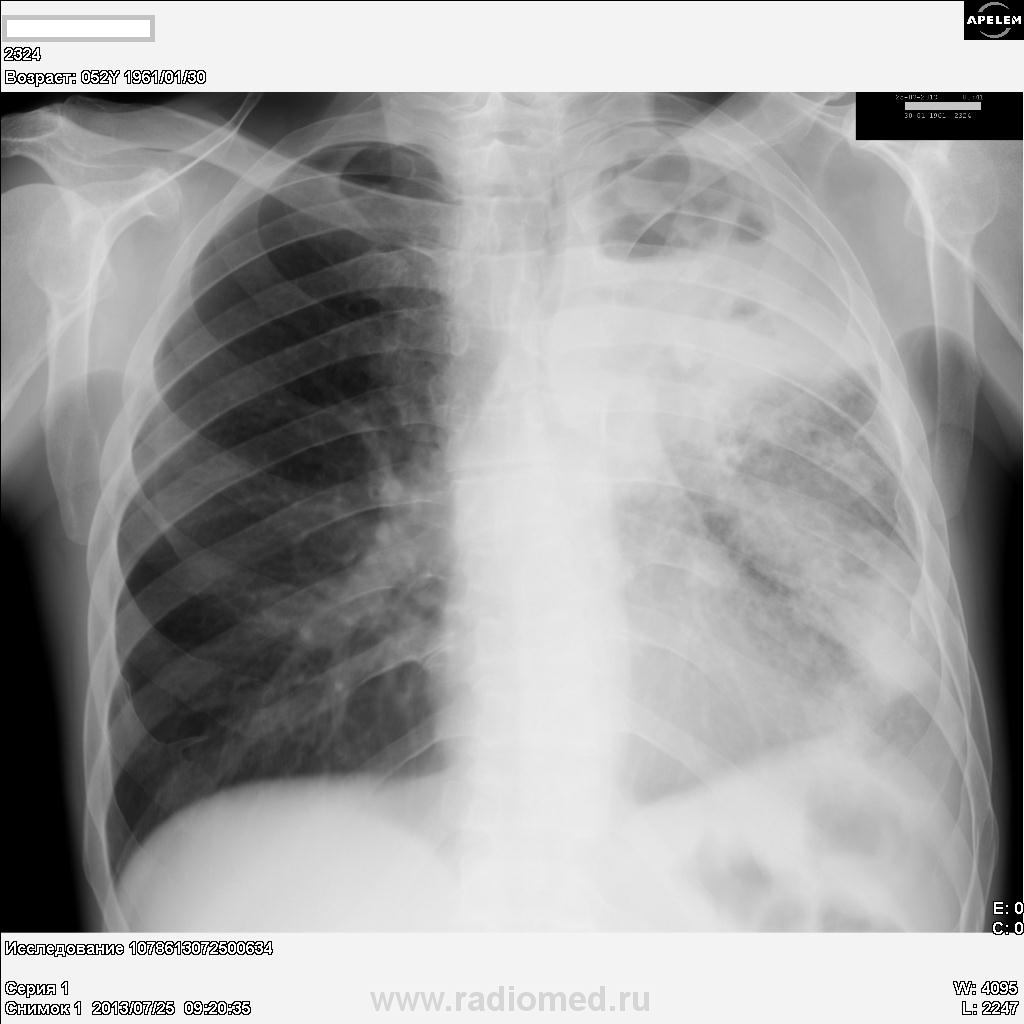

Пациент, 52 года. Поступил в т/о с диагнозом: Пневмония. Анализов еще нет. Со слов, болен три дня: кашель, слабость, небольшая лихорадка, одышка. Снимки от сегодня.

Предварительно картину можно расценить, как  полисегментрную абссцедирующую пневмонию, не исключается параканкрозный характер процесса.Показана бронхоскопия.

Деструктивная пневмония,держать в уме рак.Справа игра теней или пневмоторакс.

Я бы еще ателектаз верхней доли слева добавил...

На мой взгляд картина абсцесса

Как вариант: рентгенпризнаки абсцесса верхней доли левого легкого на фоне нарушения бронхиальной проходимости.

Левосторонняя тотальная пневмония, осложненная абсцедированием в S1-2 в фазе дренирования (горизонтальный уровень в полости распада), с преобладанием инфильтративных изменений в S1-2 и S4-5, с ограниченным гидротораксом в главной междолевой щели и гиповентиляцией легкого. Пациен, видимо, кахексичен. Неплохо бы возбудителя высеять, да и динамика интересна. Чем лечат?

Безусловно,абсцесс верхней доли слева.Есть онконастороженность,ниже абсцесса вероятны округлые тени.Туберкулёза нет.Поздравляю Вас,Дмитрий, с полученными ЛТГ.Нам,наверное,надо их не мельчить.Будем делиться дальнейшим опытом.